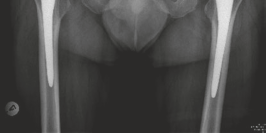

Radiographic Confirmation

Postoperative AP pelvis radiographs demonstrated bilateral uncemented THA with excellent component positioning. The acetabular shells were appropriately medialized with ideal inclination. The monobloc femoral stems were in neutral alignment, filling the metaphysis adequately without varus or valgus tilt. Leg lengths and global femoral offsets were symmetrically restored.

The lateral radiograph of the left hip confirmed appropriate anteversion of the acetabular component and central placement of the femoral stem within the medullary canal.

The lateral radiograph of the right hip similarly demonstrated excellent component alignment and seating of the uncemented monobloc stem.